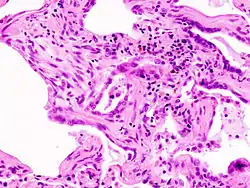

Coloration à l'hématoxyline et à l'éosine (HE).

L'interstitium (tissu de soutien) du poumon est constitué de septums interalvéolaires, situés entre les parois des alvéoles pulmonaires. Ces dernières, siège de l'échange gazeux entre sang et air, forment le tissu proprement fonctionnel du poumon (parenchyme). L'interstitium et le parenchyme coopèrent étroitement au fonctionnement du poumon, et constituent une unité fonctionnelle. L'interstitium constitue l'armature de base du poumon et soutient l'architecture des alvéoles, c'est-à-dire de la barrière sang-air pendant le cycle de la respiration. Cet interstitium est constitué de cellules, avant tout spécialisées dans le soutien (fibroblastes), de protéines structurales qu'elles produisent, et en substances telles que le collagène, les fibres élastiques, les protéoglycanes ainsi que d'autres glycoprotéines.

Le diagnostic se fait après enquête étiologique négative grâce à la combinaison de critères scanographiques et éventuellement anatomopathologies (après biopsie chirurgicale pulmonaire). L'aspect histologique typique est celui d'une UIP (de l'anglais « Usual Interstitial Pneumonia ») ou PIC en français (pneumonie interstitielle usuelle) qui se caractérise par une fibrose disséminée, des amas de fibroblastes, une distorsion architecturale marquée dans les régions septales et pleurales avec une structure en nid d'abeilles du poumon. Le modèle de l'UIP est caractéristique mais pas spécifique, et se présente dans d'autres variétés. Sur le scanner haute résolution, on parle aussi dans les formes typiques de tableau de PIC avec association de réticulations (dessins de réseaux et de lignes), d'élargissement des bronches par tractions, d'opacités floues dites en verre dépolien général peu étendues, d'aspect en nid d'abeilles dans les bases et les régions périphériques sous pleurales (destruction irréversible de l'architecture normale du poumon). Ces modifications sont le plus souvent bilatérales mais asymétriques et dans les bases des poumons.

Le type histologique est désigné comme le diagnostic clinique par LIP, et se caractérise par une infiltration des septums alvéolaires par des lymphocytes et des macrophages, ainsi que par une formation péribronchiale de tissus lymphoïdes associé aux muqueuses. Les modifiations sont distribuées de manière diffuse dans tout le poumon. À la tomodensitométrie à haute résolution, les ombres laiteuses sont caractéristiques.